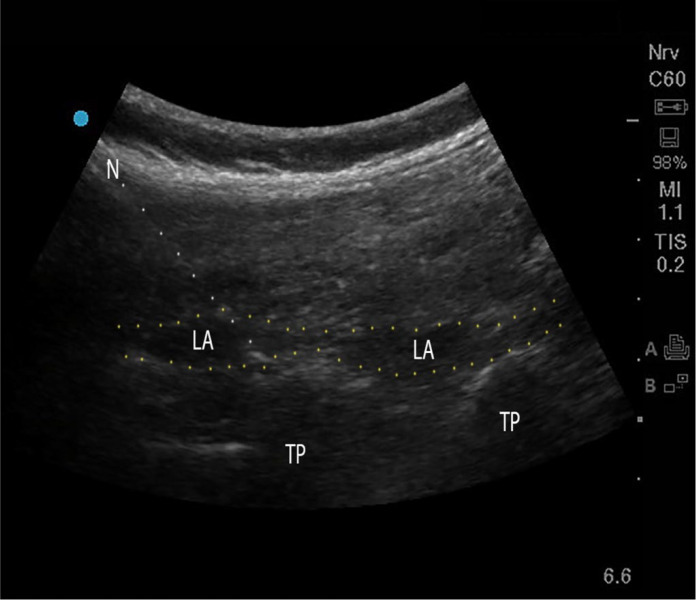

Introduction: The erector spinae plane block (ESPB) is a novel regional anesthesia technique that is increasingly incorporated into multimodal analgesia as part of enhanced recovery after surgery (ERAS) pathways in various surgical procedures, including spine surgery.

Case presentation: We report the successful use of spinal anesthesia (SA), ESPB, and magnesium sulfate in a high-risk patient with systemic sclerosis and pulmonary fibrosis undergoing laminectomy. A multimodal approach was selected due to the patient's underlying condition. This strategy minimized respiratory complications associated with general anesthesia while providing effective surgical anesthesia and postoperative pain control without opioid-related complications.

Conclusions: Our case highlights the utility of ESPB, not only for postoperative pain management but also as a valuable adjunct to primary anesthesia, especially in high-risk patients.